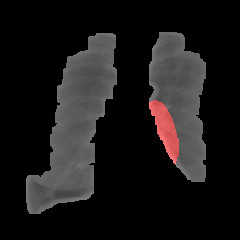

Refer to caption

Figure 2: Stages of image preprocessing computer vision algorithm

Preprocessing The PLCO image dataset had roughly 200,000 CXRs with an approximate size of 2000x3000 pixels. In [9], down-scaling and cropping led to an improvement in their results, leading us to adopt similar procedures.

In the provided dataset, there were around 4,000 images that were linked with patients having biopsy-proven lung cancer. We used these images to create our cancer dataset, using an additional 4,000 other images as control/negative. Each of our datasets were then preprocessed to make the images uniform and to ensure the models were not influenced by other noise, such as notes or markings.

The first step was resampling and resizing the images to a constant 256x256 resolution, as this would retain enough detail for effective use and eliminate the inconsistencies seen in the input data. The second step involved a specially-designed x-ray lung segmentation algorithm that was used to mask the input images to contain only the regions of interest. Initially, the images were shifted to have a constant mean, which was required due to the variation in images coming from different medical centers using different models of x-ray machines. Next, the images were filtered to retain only the middle intensities, which were found to correspond with the inside of the lungs. Contours were then extracted from the remaining part of the image which were then filled in to create the final mask for that image, which was then applied. The steps used in this procedure are as shown in figure 2.

Finally, the entire masked dataset as a whole was rescaled to a standard normal distribution which was then shuffled and randomly split into a training dataset containing 80% of the final images, a validation dataset containing 10%, and the last 10% reserved for evaluating the final trained model.